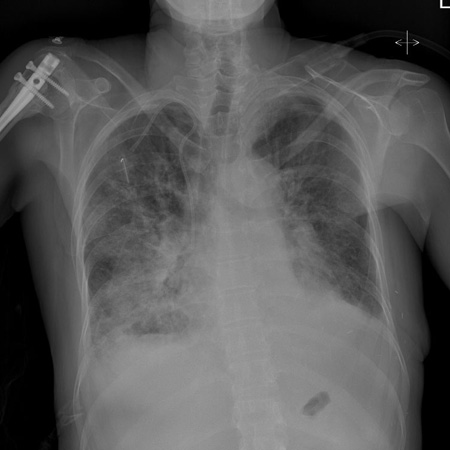

Radiografia torácica

O National Institute for Health and Care Excellence do Reino Unido recomenda uma radiografia torácica para todos os pacientes com suspeita de insuficiência cardíaca.[29] Procure por:[34]

Congestão pulmonar

Derrame pleural

Líquido intersticial ou alveolar na fissura horizontal

Cardiomegalia

Practical tip

Esteja ciente de que uma disfunção ventricular esquerda significativa pode estar presente sem cardiomegalia na radiografia torácica.[34]

[Figure caption and citation for the preceding image starts]: Radiografia torácica de edema pulmonar agudo mostrando aumento dos marcadores alveolares, fluido na fissura horizontal e redução dos ângulos costofrênicosDos acervos particulares de Syed W. Yusuf, MBBS, MRCPI, e Daniel Lenihan, MD [Citation ends].

[Figure caption and citation for the preceding image starts]: Radiografia torácica mostrando edema pulmonar agudo com marcadores alveolares aumentados e derrames pleurais bilateraisDos acervos particulares de Syed W. Yusuf, MBBS, MRCPI, e Daniel Lenihan, MD [Citation ends].